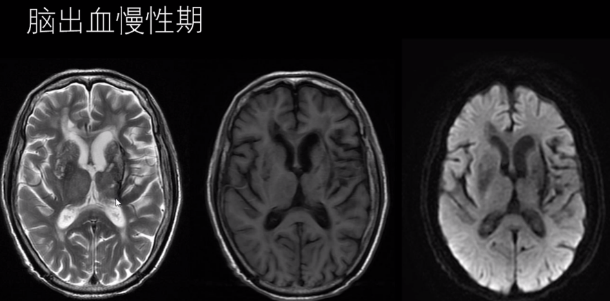

(4)慢性期 CT 囊性病灶,可见钙化;T2WI 高信号血肿周围被低信号含铁血黄素包饶。